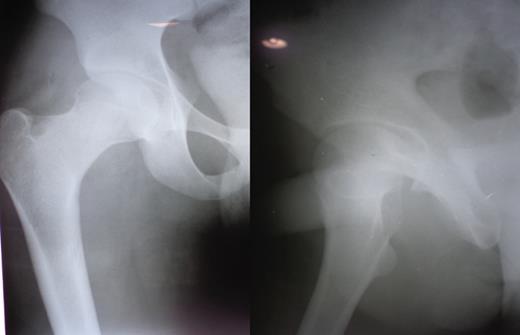

A 23-year-old male pavement dweller was brought to the emergency department of this hospital after being hit by a tempo. The patient was in a state of shock with an open right-sided anterior hip dislocation with the femoral head being visible in the inguinal region (Fig. 1). The neurovascular status of the right lower limb was intact. Immediate resuscitation was done and hip radiographs (Fig. 1) were taken, which showed an anterior-inferior dislocation with an inferior pubic ramus fracture on the left side. The patient was immediately transferred to the operating room where the wound was thoroughly debrided and the femoral head was relocated within 5 hours of sustaining the trauma (Fig. 2). The wound after surgical debridement was 8 × 6 cm in dimensions, which was primarily closed after checking for the stability of the reduction. The patient was started on intravenous metronidazole, amikacin and ceftriaxone for 5 days, followed by oral amoxicillin for a week. The patient was kept non-weight-bearing on skin traction for 6 weeks. The wound healed satisfactorily with no evidence of infection, nor any episode of re-dislocation at 6 months (Fig. 3). The patient was unfortunately lost to follow-up.